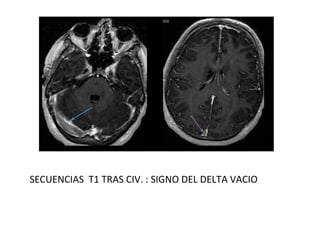

SECUENCIAS T1 TRAS CIV. : SIGNO DEL DELTA VACIO

SECUENCIAS T1 TRASCIV. : SIGNO DEL DELTA VACIO

• TC CON CONTRASTE IV

SIGNOS DIRECTOS

- Signo del delta vacío: es el signo directo más frecuente, se

observa hasta en un 30% de los casos.

- Ectasia venosa.

• SECUENCIAS CONVENCIONALES:

- En la TVC subaguda se observa la señal hiperintensa en el

interior del seno afectado en secuencias potenciadas en T1.

- Confirmar con secuencias en diferentes planos o realizar un

estudio postcontraste que demuestre el signo delta.

- El trombo venoso presenta cambios de señal a lo largo del

tiempo.